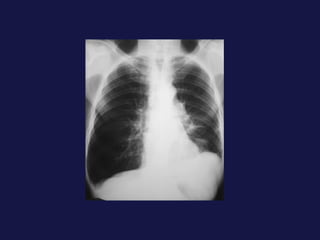

Hallazgos radiológicos. Tumor periférico. Nódulo o masa pulmonar. Bordes definidos, lobulados, irregulares, espiculados Calcificación ( focal, excéntrica ) Cavitación 1% presentan nódulos satélites. 25%  de broncoalveolares son múltiples. Adenocarcinoma y carcinoma de células alveolares.

Hallazgos radiológicos. Tumorperiférico. Nódulo o masa pulmonar. Bordes definidos, lobulados, irregulares, espiculados Calcificación ( focal, excéntrica ) Cavitación 1% presentan nódulos satélites. 25% de broncoalveolares son múltiples. Adenocarcinoma y carcinoma de células alveolares.